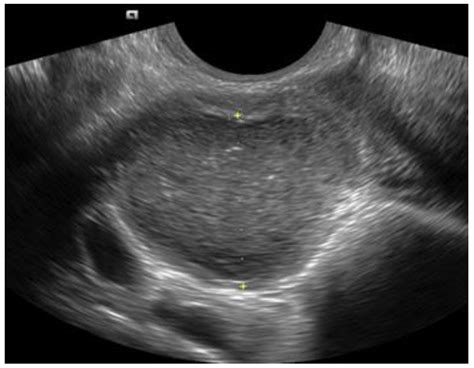

A transvaginal ultrasound is a diagnostic imaging procedure used to examine the internal female reproductive organs. Unlike an abdominal ultrasound, which uses a transducer pressed against the skin of your stomach, a transvaginal ultrasound involves inserting a specialized, slim probe into the vagina. This allows the medical professional to get a much closer, clearer view of the uterus, ovaries, cervix, and fallopian tubes.

This imaging method is highly effective because the transducer is positioned closer to the pelvic organs, providing higher-resolution images compared to external methods. It is commonly used to: